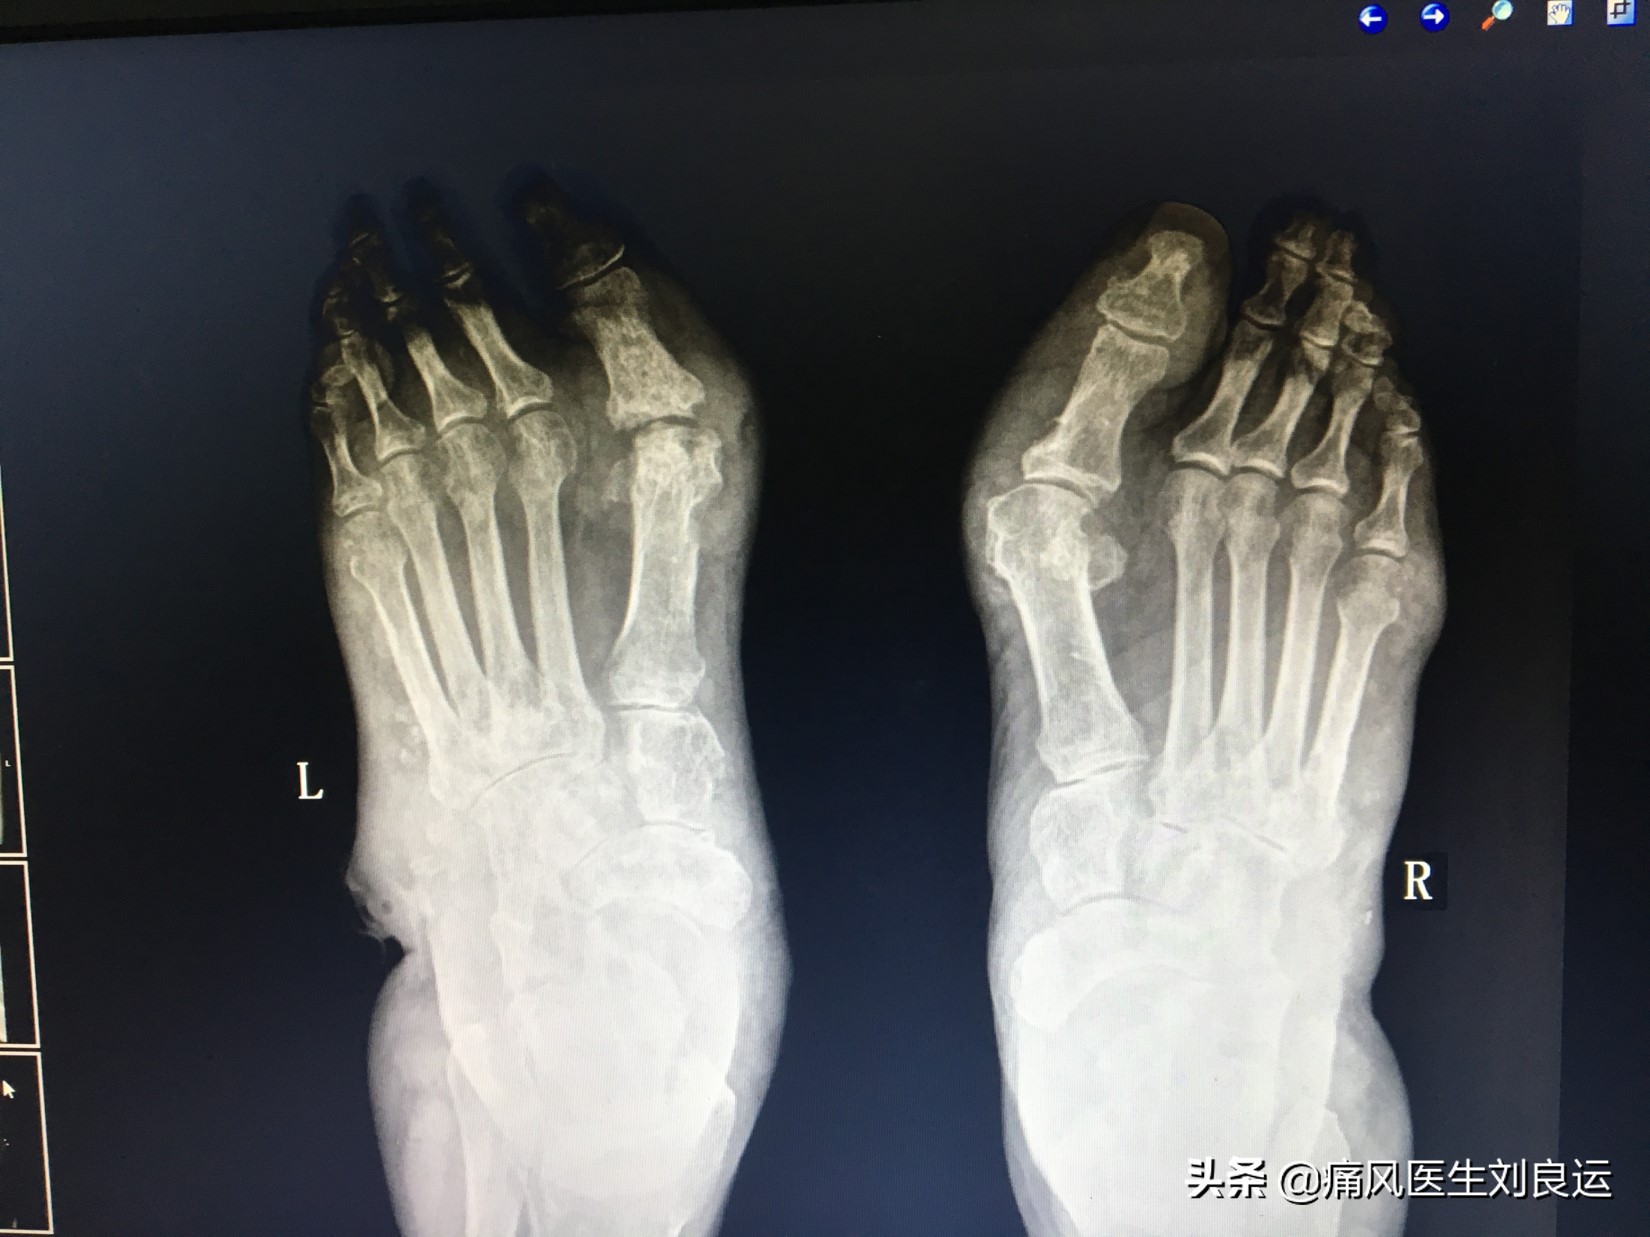

X线下双足痛风石

痛风石是痛风的特征性改变,痛风石的形成与病程、血尿酸水平有关。病程越长,发生痛风石的几率就越大。高尿酸血症持续时间越长,越易发生痛风石。反之,痛风石越多、越大,表明高尿酸血症未得到很好控制,即病情越重。有些患者,病程虽己很长,但治疗后血尿酸长期保持在正常范围内,很少发生痛风石。痛风石不同病情有不同的临床表现: